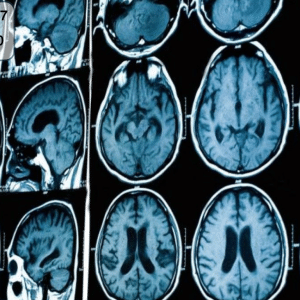

قراءة أشعة الرنين المغناطيسي للمخ ليست مجرد خطوة طبية روتينية، بل هي نافذة تُظهر أدق تفاصيل الدماغ، وتكشف الكثير مما لا يمكن رؤيته في الأشعة

جهاز الرنين المغناطيسي أصبح اليوم من أهم الأجهزة الطبية في العالم، إذ لا يخلو أي مستشفى حديث منه. فهو يعتبر بمثابة “العين الثالثة” للطبيب التي

التكنولوجيا الطبية تتطور بسرعة مذهلة، ومن بين أبرز هذه التقنيات التي غيّرت مفهوم التشخيص الطبي هي تقنية رنين مغناطيسي. هذه التقنية المذهلة تمكّن الأطباء من